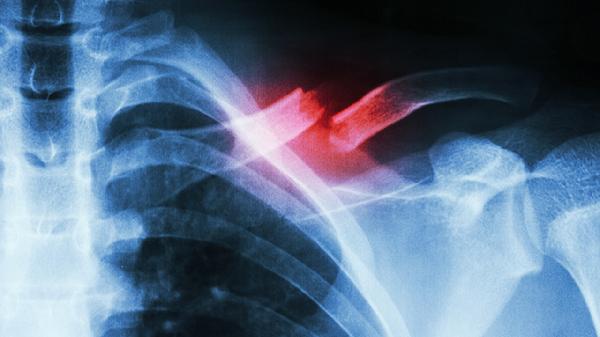

肋骨骨折多数情况下可以短距离缓慢行走,但需避免剧烈运动、咳嗽时按压患处、使用胸带固定、严格遵医嘱用药。

1、避免剧烈运动

骨折初期应限制活动幅度,行走时保持匀速步伐,防止骨折端移位加重疼痛或损伤肺组织。

2、咳嗽时按压患处

咳嗽或打喷嚏前用手掌轻压骨折部位,可减少胸廓震动幅度,降低尖锐骨茬刺伤胸膜的风险。

3、使用胸带固定

弹性胸带能限制胸廓过度扩张,建议在医生指导下调整松紧度,夜间睡眠时可适当放松。

4、遵医嘱用药

疼痛明显时可遵医嘱使用洛索洛芬钠片、塞来昔布胶囊或对乙酰氨基酚缓释片等镇痛药物。

恢复期间建议保持低盐高蛋白饮食,适量补充维生素D促进骨愈合,若出现呼吸困难或持续剧痛需立即就医。